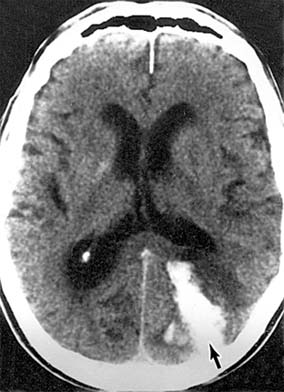

Figure 14-28

Figure 14-28: Occipital hematoma (arrow) resulting from a bleeding arteriovenous malformation. This lesion produced homonymous hemianopia and headache.